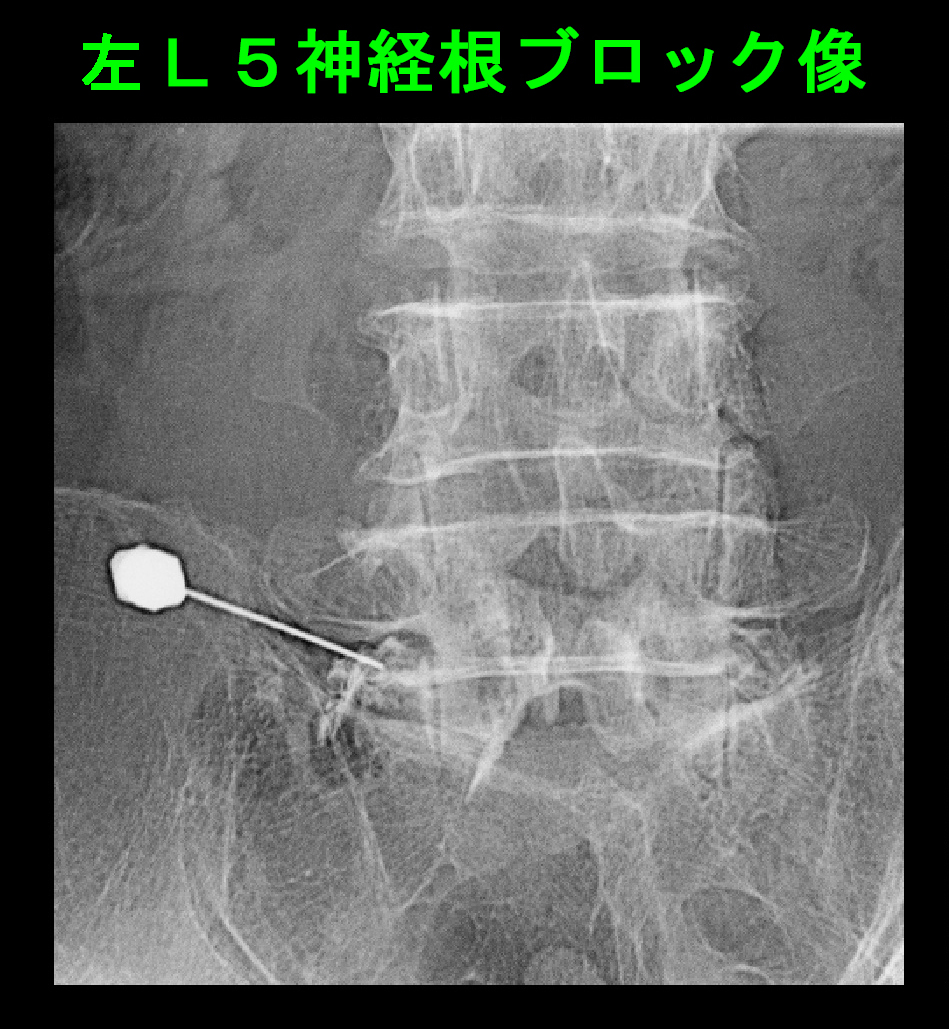

腰椎のMRI検査では、L4-5で脊髄の圧迫の所見が認められ、そこで障害されている左L5神経根にブロックを行い、症状の軽減がえられました。

2013.4.16.C.jpg2013.RB2b.jpg